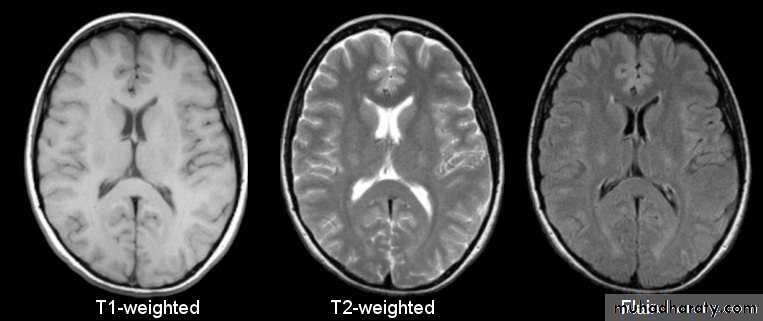

Tissue contrast and imaging sequences:

Much of the complexity of MRI arises from the fact that the MR signal depends on many varied properties of the tissues and structures being examined, including:• Number of hydrogen atoms present in tissue (proton density)

• Chemical environment of the hydrogen atoms, e.g. whether in free water or bound by fat• Flow: blood vessels or CSF

• Magnetic susceptibility

• T1 relaxation time

• T2 relaxation time.

By altering the duration and amplitude of the RF pulse, as well as the timing and repetition of its application, various imaging sequences use these properties to produce image contrast. Terms used to describe the different types of MR imaging sequences include spin echo, inversion recovery and gradient-recalled echo (gradient echo).

Spin echo sequences

• Spin echo sequences include T1-weighted, T2- weighted and proton density.

• Following the application of a 90° RF pulse, the net magnetization vector lies in the transverse plane. Also, all of the hydrogen protons are ‘in phase’, i.e. spinning at the same rate. Upon cessation of the RF pulse, two things begin to happen:

• Net magnetization vector rotates back to the longitudinal direction: longitudinal or T1 relaxation

• Hydrogen atoms dephase (spin at slightly varying rates): transverse or T2 relaxation (decay).